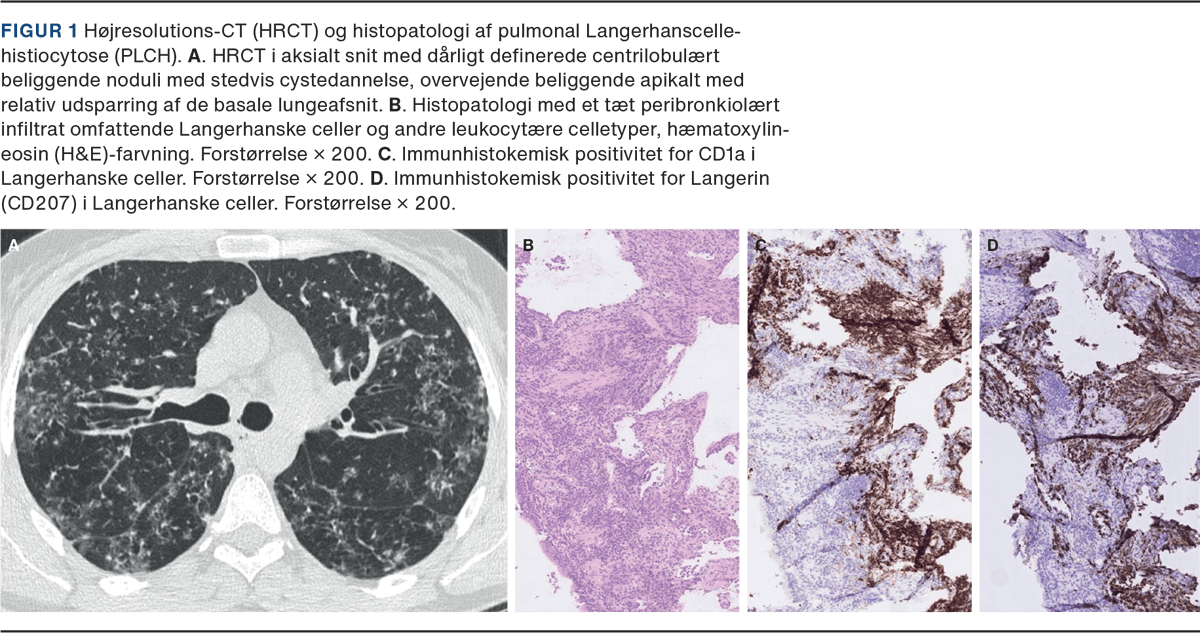

HRCT viser typisk bilaterale basale matglasforandringer ofte med emfysem og mindre hyppigt cystiske forandringer. Der ses ofte fin retikulering i områderne og forvridning af arkitekturen (Figur 3) [16]. Histologisk ses ensartet diffus ophobning af pigmenterede makrofager i alveolerne med let interstitiel inflammation, men uden tydelig fibrose og med bevaret lungearkitektur [17].